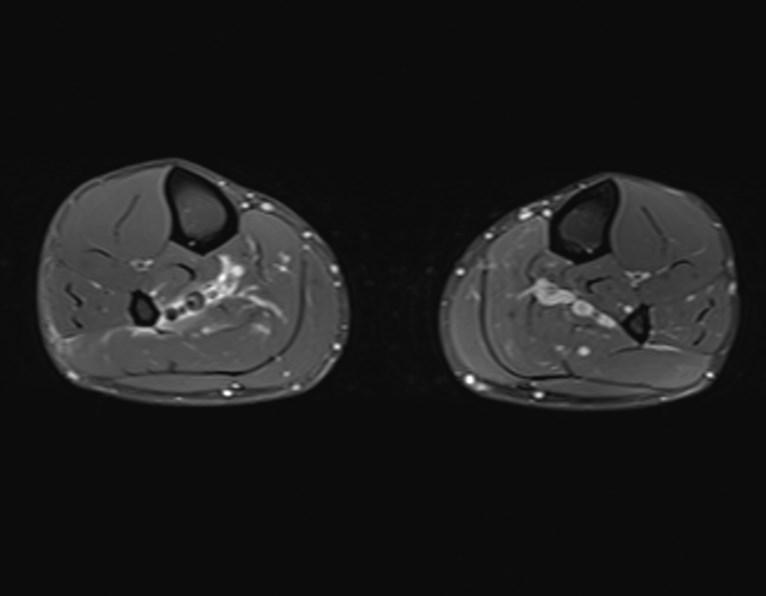

*29-year-old male present with pain in the right lower extremity for 3 days.

What is the most likely diagnosis?

Answer: Crural deep vein thrombosis

MR images showed perivascular edema, perifascial edema and the deep crural venous filling defects.